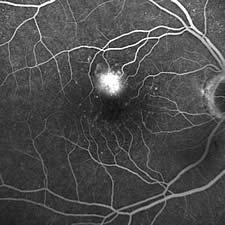

Diagnostik - Angiographie

Die Fluoreszenz-Angiographie (Gefäßdarstellung der Netzhaut mit einem fluoreszeierenden Farbstoff) ist das wichtigste diagnostische Verfahren in der Augenheilkunde. Es wird heute bei fast allen Patienten, die an einer Erkrankung der Netzhaut oder der Makula (Stelle des schärfsten Sehens der Netzhaut) leiden, durchgeführt. Zur Angiographie wird dem Patienten eine kleine Menge eines fluoreszeierenden und vollkommen ungiftigen Farbstoffs in eine Armvene injiziert. Nach etwa 20 Sekunden erscheint der Farbstoff am Augenhintergrund und wird dort mit einer sehr lichtempfindlichen Laserkamera photographiert. Die Lichtbelastung des Auges ist hierdurch ausgesprochen gering und die Untersuchung für den Patienten nicht belastend. Mit der Angiographie lassen sich Veränderungen der Netzhautgefäße wie Entzündungen, Thrombosen oder Embolien, eine Wassereinlagerung in der Netzhautmitte (Makulaödem), Membranbildungen auf der Netzhaut oder Veränderungen der Pigmentschicht des Augenhintergrundes feststellen. Am wichtigsten ist die Angiographie bei der Unterscheidung der trockenen von der feuchten Form der alterskorrelierten Makuladegeneration, weil bei der feuchten Makuladegeneration heute eine rasche und effektive Therapie in Form einer intraokularen Injektion eines Gefäßhemmstoffs möglich ist. Für besonders schwierig zu diagnostizierende Erkrankungen steht uns mit der Infrarot-Angiographie ein zweites diagnostisches Verfahren zur Verfügung, mit dem der Beginn einer feuchten Makuladegeneration oft früher erfasst werden kann als mit der Standard-Angiographie. |